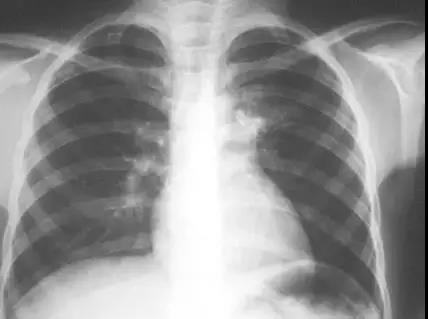

警惕肺结核

肺结核由于起病缓慢,早期肺结核病人症状不甚明显,除经常“感冒”外,消瘦,低热是不可忽略的症状。

故对于反复“感冒”不愈或感冒样症状迁延两周以上伴有消瘦的人,应去医院作X线检查及痰检,以明确诊断有无肺结核。